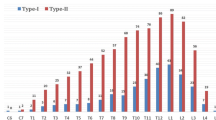

From 2011 to 2017, 24 patients (9 males and 15 females; age, 10–24 years; average age, 16.38 ± 4.56 years), suffered from RCS associated with SCM, were treated at our Department. In all patients X-ray, CT and MRI examinations revealed: the apex of the deformity was lumbar (n = 9), thoracic (n = 11), and thoracolumbar (n = 4); based on CS classification, all patients were divided into 3 types, including 13 cases of failure of segmentation, 4 cases of failure of formation, and 7 cases of mixed defects; based on SCM classification, all patients were divided into 2 types, including 14 cases of SCM type 1 and 10 cases of SCM type 2; only 7 patients had complication of syringomyelia. Thorough neurological examination, including muscle strength, sensation, pathological and physiological reflexes, was carried out in all of the patients. No apparent neurologic dysfunction was found before surgery. Only 1 patient complained of irregular urination, and thus underwent additional neural electromyography and urodynamic test. Based on all normal results of tests, this patient was also included in this study. The Ethics Committee of Xiangya Hospital of Central South University approved the study. All methods were performed in accordance with the relevant guidelines and regulations. Informed consent for study participation was obtained.

Somites, which vertebrae derived from, enclosed neural tube during embryonic development. Any injury resulting in vertebral deformity during embryonic development may cause neural tube defects. Therefore, CS is usually accompanied by intraspinal anomalies, including SCM, tethered cord, syringomyelia, Arnold Chiari malformation, etc. There may also be multiple intraspinal anomalies at the same time [11, 12]. In fact, CS and SCM usually occurred simultaneously in clinical practice. According to report, SCM was observed in 4.0 to 9.0% of patients with CS. The dorsolumbar and lumbar regions are the most common sites. The clinical symptoms could be summarized as following characteristics: lower extremity weakness, atrophy, and deformity, scoliosis, spinal bifida, skin lesions, sphincter dysfunction [13, 14].